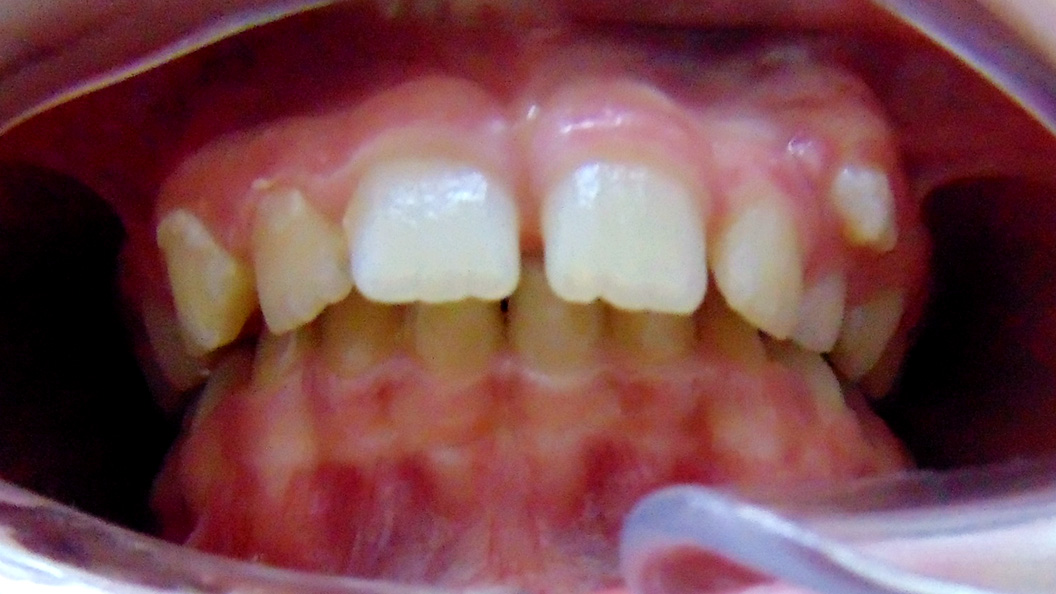

Родители пациента обратились в «Стоматологию Комфорта» для исправления неправильного прикуса у ребёнка 11-и лет. Врач-ортодонт Резниченко Анна Васильевна провела осмотр и установила, что у пациента наблюдается суперпозиция 23 зуба и вертикальная резцовая окклюзия. Врачом было принято решение о целесообразности лечения съёмным аппаратом-ортокорректором Occlus-o-Guide.